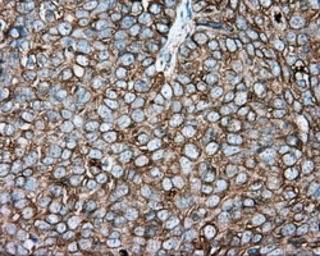

IHC-P analysis of human endometrium adenocarcinoma tissue using GTX83462 alpha Tubulin 8 antibody [2G6].

IHC-P analysis of human ovary adenocarcinoma tissue using GTX83462 alpha Tubulin 8 antibody [2G6].

Antigen retrieval : Heat-induced epitope retrieval by 10mM citrate buffer, pH6.0, 100ºC for 10min.

Dilution : 1:50